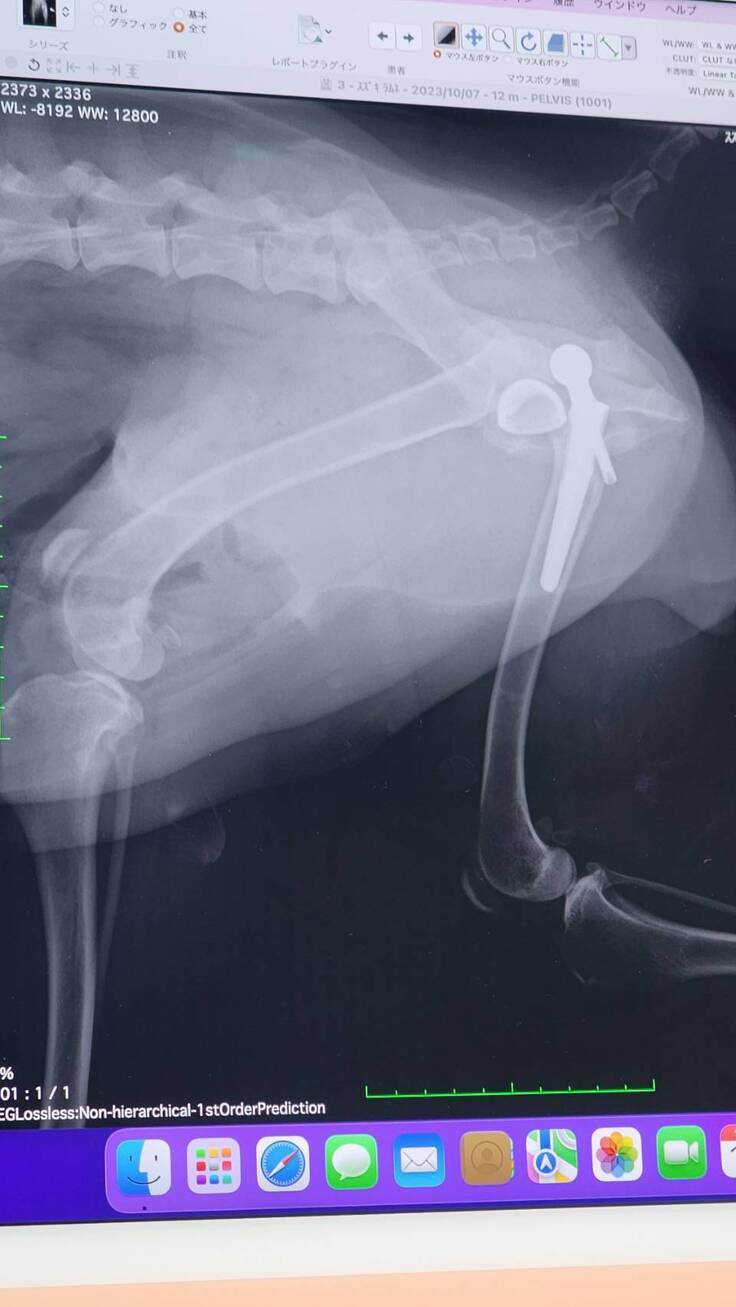

退院予定日の2日前に病院から連絡が入り、人工股関節が脱臼してしまっていると報告を貰いました。

緊急で昨日再手術があり本日10/13が退院予定日でしたが、病院で現状と今後の説明がありました。

もともと亜脱臼状態で生活していたため筋肉もそのように作られており人工股関節に違和感がありはずれてしまった。さらに人が好きすぎて看護師さんを見ただけでもはしゃいでおりそのタイミングで外れてしまった。いくつかの過程を聞き最後に。。。